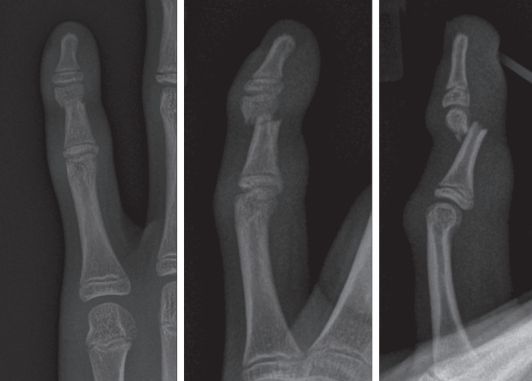

- Закрытая репозиция и чрескожная фиксация спицами Киршнера или аппаратами внешней фиксации. Этот малоинвазивный метод позволяет без открытого вмешательства аккуратно вправить отломки и зафиксировать их проведёнными через кожу металлическими спицами. При этом пациенты могут сгибать дистальный межфаланговый сустав, однако не могут активно его разгибать.

![Лечение перелома средней фаланги безымянного пальца кисти спицами Киршнера [6] Лечение перелома средней фаланги безымянного пальца кисти спицами Киршнера [6]](/media/bolezny/perelom-palca/lechenie-pereloma-srednyay-falangi-bezymyannogo-palca-kisti-spicami-kirshnera-6_s_joj3beW.jpeg?dummy=1777378745495)

Лечение перелома средней фаланги безымянного пальца кисти спицами Киршнера [6]